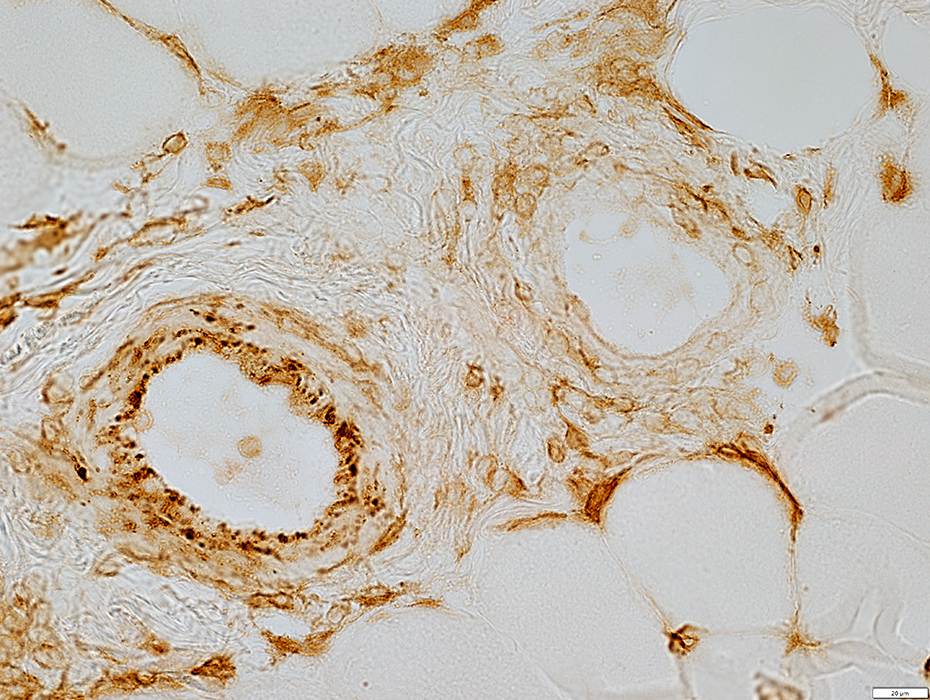

MHC Class I stain

MHC Class I

Mildly increased on muscle fiber surfaces

MHC Class I stains cells in & around vessel walls

Alkaline phosphatase stains connective tissue in perimysial vessel

Alkaline Phosphatase stain